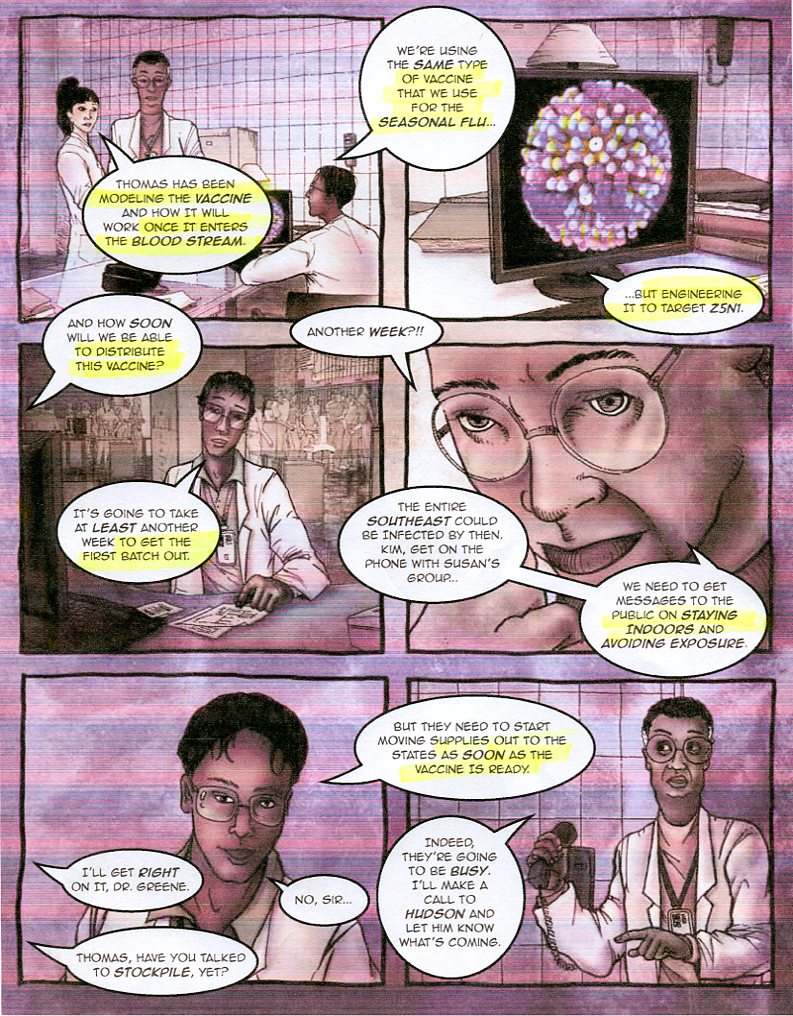

(CDC center for controlling disease)

Preparedness 101: Zombie Pandemic